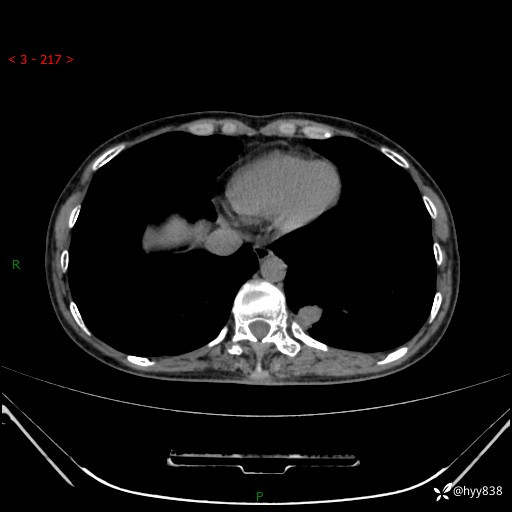

胸部CT平扫

增强动脉期+静脉期

各期CT值:48hu 65hu 76hu